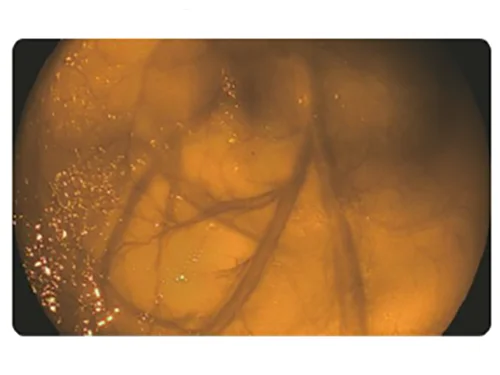

Улучшенная визуализация гемоглобина (HEI)

Улучшенная визуализация гемоглобина (HEI)

Выявление глубоких сосудов, контроль источников кровотечения.

HEI: Улучшенная визуализация гемоглобина

Сочетание узкополосного красного, зеленого и желтого цветов улучшает видимость глубоких кровеносных сосудов и точек кровотечения за счет использования алгоритма слияния изображений и технологии автоматической обработки.

Применение

- Выявление кровотечений (упрощает остановку интраоперационных кровотечений)

- Визуализация варикозно расширенных вен для проведения лечения (упрощает обнаружение целевых вен при инъекционном лечении или перевязке вен).

HEI